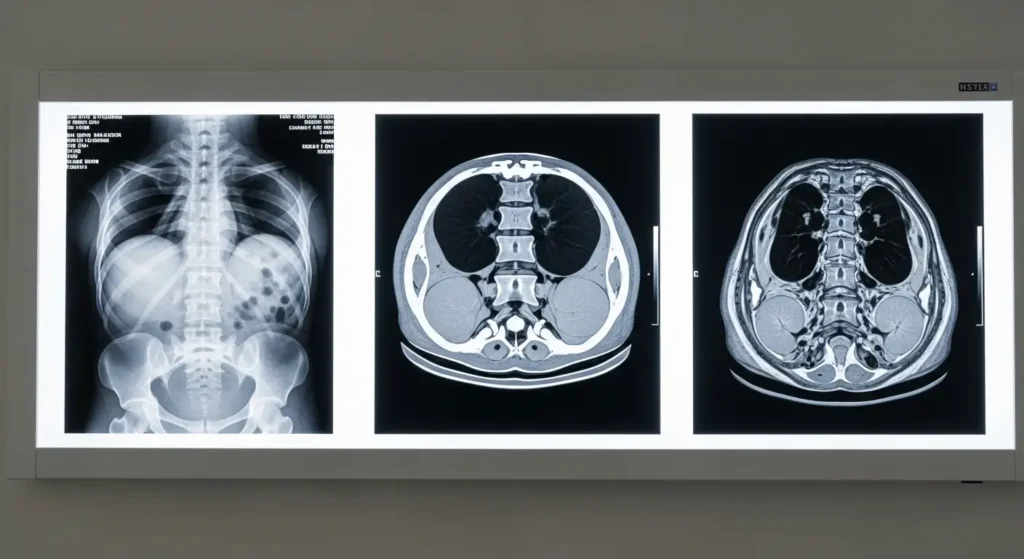

La tomodensitométrie lombaire, plus connue sous le nom de Scanner lombaire ou TDM lombaire, est un examen d’imagerie médicale qui prend des « photos en tranches » très fines de votre colonne vertébrale basse. Imaginez un pain de mie que l’on coupe en tranches millimétriques — le scanner fait exactement cela avec votre dos, permettant au radiologue d’examiner chaque structure en détail sous tous les angles, y compris en reconstruction 3D.

Concrètement, cet examen permet de visualiser :

- Les 5 vertèbres lombaires (numérotées L1 à L5)

- Le sacrum, l’os qui relie votre colonne au bassin

- Les disques intervertébraux, ces coussinets amortisseurs entre chaque vertèbre

- Le canal rachidien, dans lequel passe la moelle épinière et les nerfs

- Les racines nerveuses qui partent de la colonne vers les jambes

- Les muscles et tissus mous environnants